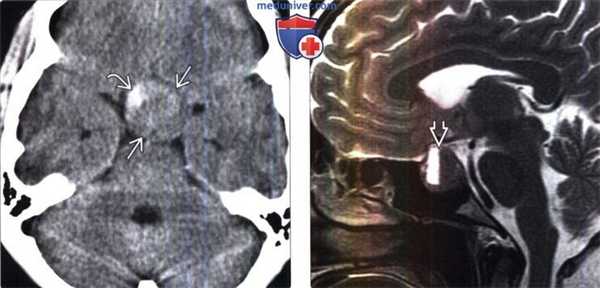

(Слева) Бесконтрастная КТ, аксиальный срез: у пациента с острой интенсивной головной болью и битемпоральной гемианопсией в супраселлярной цистерне визуализируется преимущественно изоденсное объемное образование. При операции было выявлено кровоизлияние в периферические отделы крупной макроаденомы.

(Справа) МРТ, Т2-ВИ, сагиттальный срез: у пациента с ранее диагностированной пролактин-секретирующей макроаденомой (проводилось лечение агонистом дофаминовых рецепторов (каберголин)), определяется уровень раздела кровь-жидкость. Пациент поступил в лечебное учреждение с жалобами на острое развитие головной боли и ухудшение зрения.

(Слева) МРТ, Т2-ВИ, корональный срез: у мужчины 60 лет с апоплексией гипофиза и жалобами на головную боль, острые зрительные нарушения и тошноту визуализируется гиперинтенсивное селлярное и супраселлярное образование с гипоинтенсивным ободком. Обратите внимание на смещение кверху зрительного перекреста.

(Справа) МРТ, постконтрастное Т1 -ВИ, режим подавления сигнала от жира, корональный срез: у этого же пациента определяется объемное образование селлярной/супра-селлярной областей с зоной центрального некроза и накоплением контрастного вещества по периферии - картина апоплексии гипофиза. Обратите внимание на смещение кверху зрительного перекреста.